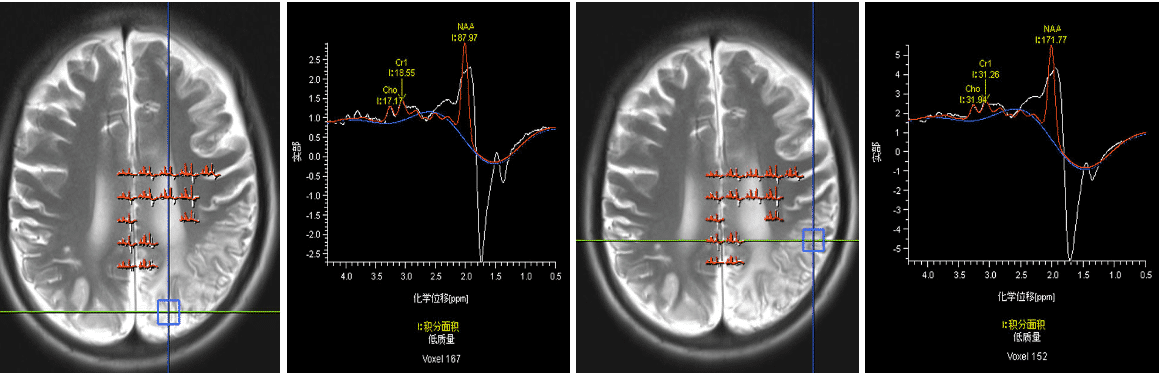

图3,磁共振波谱分析(MRS):感兴趣区NAA峰减低,Cho峰减低,在1.33出现高耸倒置Lac峰。